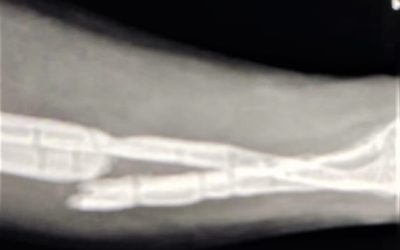

Osteocondritis medial del astrágalo en el tobillo: qué es

Feb 22, 2025

Lo que debes saber sobre el diagnóstico, tratamiento y recuperación de la osteocondritis medial del astrágalo La...